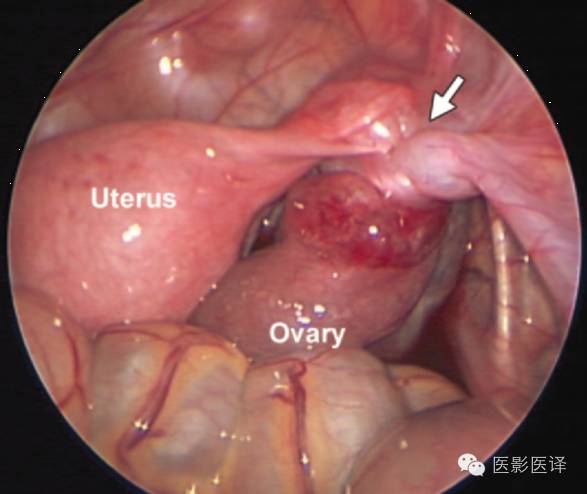

生后囊肿抽吸术可以减少扭转的几率,且争议较少,因为胎儿出生后诊断更加明确,手术并发症风险更小,因此生后囊肿抽吸术的“价值和安全性是明确的”。新生儿卵巢囊肿达4-5cm或是更大者,应该考虑卵巢抽吸术。生后卵巢囊肿最保守的治疗是观察一段时间,因为卵巢囊肿可能会自发缩小。生后新生儿应该每4-6周进行一次超声检查,直到卵巢囊肿消失、增大、出现症状或持续6个月无变化。手术指征通常包括复杂性、有症状、持续增大及超过6个月的囊肿。Zampieri等发现大于5cm的囊肿通常需要手术治疗。新生儿卵巢囊肿进行腹腔镜术后是可行且安全的。对于巨大卵巢囊肿,为了保存卵巢功能,应该行保守手术治疗,如囊肿剥除术或开窗术。如果观察期间发生卵巢扭转,可以尝试卵巢扭转矫正法来保存卵巢功能(图21)。如果扭转可能导致败血症或血流动力学不稳定,应该考虑行卵巢切除术和输卵管-卵巢切除术。

图21.卵巢扭转。新生儿的术中图片显示子宫、左侧肾上腺及扭转的卵巢蒂(箭)。腹腔镜复位术顺利.